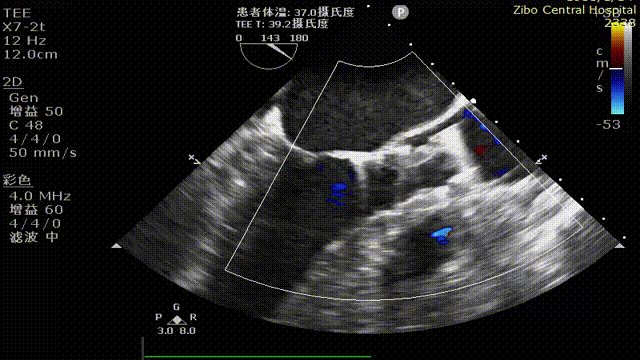

患者为75岁老年男性,主诉“间断性胸闷2个月”入院,临床主要诊断为“主动脉狭窄(重度)合并右冠狭窄、小左室”。既往患高血压40年,“冠心病”病史30余年,患有糖尿病20年,脑梗死后遗症20年,慢性阻塞性肺疾病8年,左侧肢体活动欠灵活。入院超声提示重度主动脉瓣狭窄,主动脉根部直径21mm,窦部直径27mm,左室射血峰值流速5.05m/s,主动脉平均跨瓣压差49mmHg。CT报告示主动脉瓣钙化明显,左右冠存在明显钙化斑块,左室前后径28.7mm。

主动脉根部评估:

CT数据显示该患者为三叶三窦式主动脉瓣。

1. 主动脉瓣瓣环周长70.6mm,平均周长径 22.5mm,SOV:28.5mm*28.7mm*29.9mm,瓣叶增厚,瓣上钙化明显。

2. 左冠开口高度14.3mm,右冠开口高度16.4mm,高度可,根据瓦氏窦内径和瓣叶长度综合判断,冠脉堵塞风险小,双侧冠脉钙化严重。

钙化评估:

中度钙化,HU850积分472m㎡,RCC钙化最严重,其次为LCC、NCC。

心室情况:

左室前后径28.7mm,左室最小径13.6mm,瓣环下6mm存在心肌膨出,